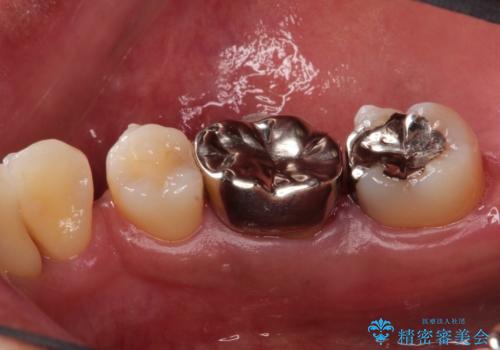

- 奥歯が痛いことを主訴に来院されました。

遠心根に歯根破折を認め、保存不可と判断しブリッジにて欠損補綴を行なっております。